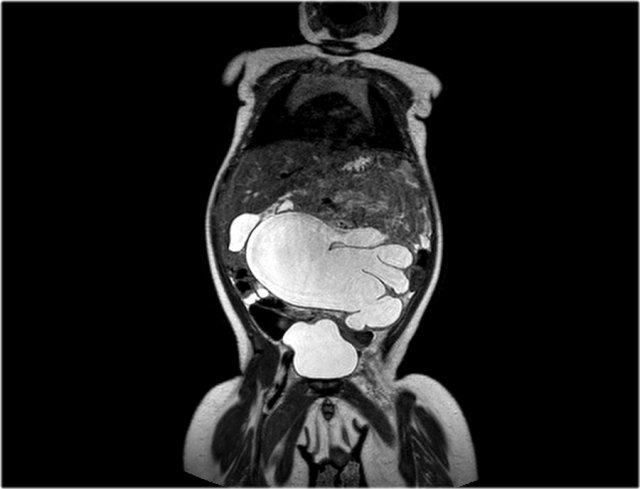

Đây là hình ảnh của một bé gái 1,5 tuổi có khối u sờ thấy được ở bụng trái.

Siêu âm cho thấy một khối u lớn cấu thành bởi vô số nang, xuất phát từ thận trái.

Trên ảnh MRI mặt phẳng trán chuỗi xung T2W, các nang được hiển thị rõ ràng.

Phần còn lại của thận trái nằm ở phía đuôi của khối u.

Kết quả giải phẫu bệnh xác định là u nguyên bào thận dạng nang biệt hóa một phần.